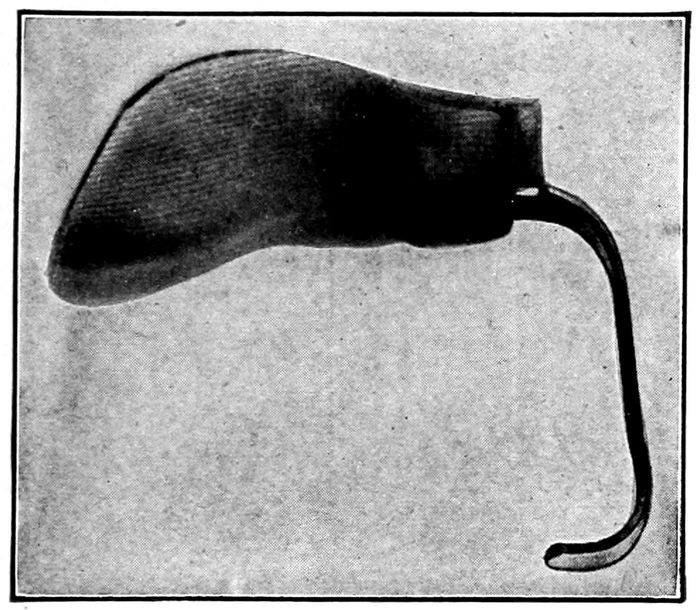

A standard nipple shield |

246 |

| |

| 110. |